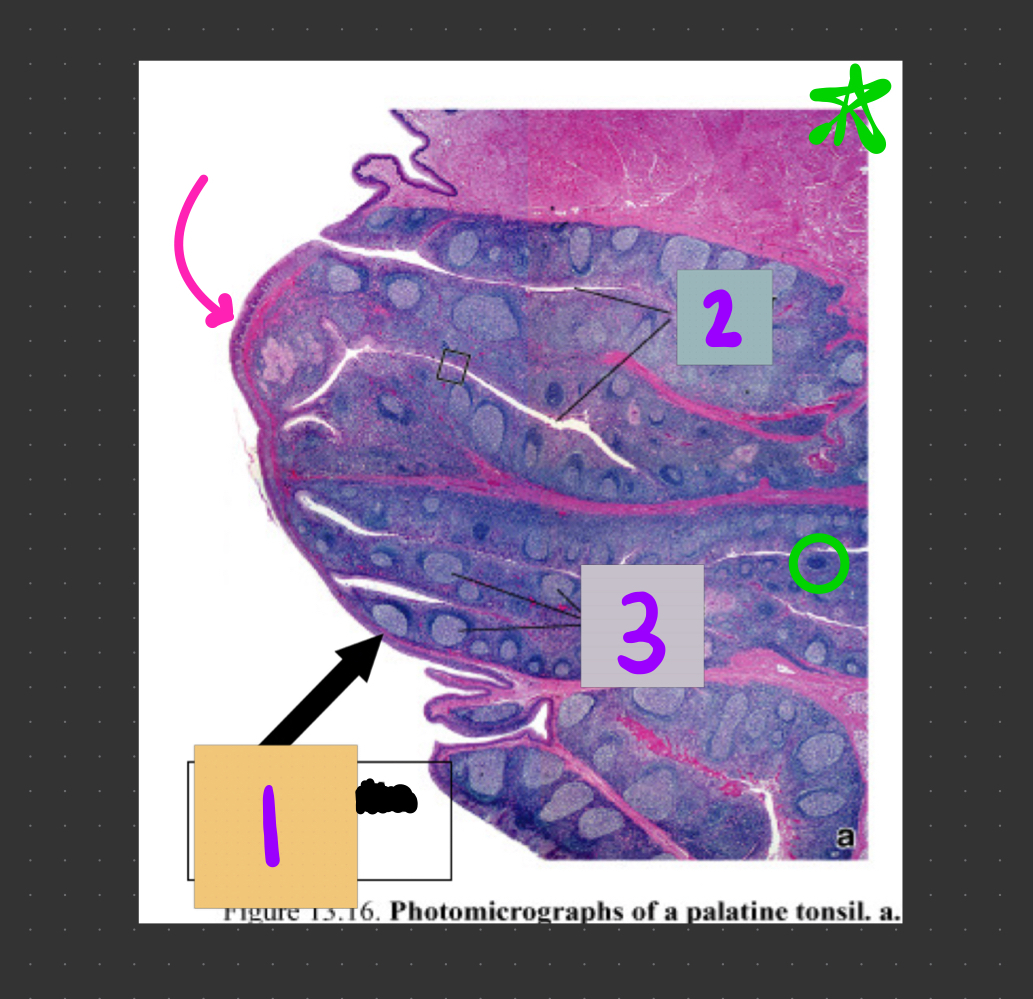

1

Q

What is #1?

A

1° lymphoid nodule

dark color, no germinal center

2

What is #2?

3

What is #3?

How well did you know this?

Not at all

4

5

Perfectly

What is #4?

2° lymphoid nodule

light color, has a germinal center

2° is bigger than 1°, has germinal center

6

1° is smaller than 2°, no germinal center

7

What structure is circled in red?

active 2° lymphoid nodule with germinal center

8

What type of epithelium is the pink arrow pointing to?

stratified squamous epithelium

9

What structure is #1?

lymphatic nodule

10

What structures are #2?

tonsilar crypts

11

What structures are #3?

lymphatic nodules

12

What structure is circled in green?

1° lymphoid nodule (inactive) = no germinal center